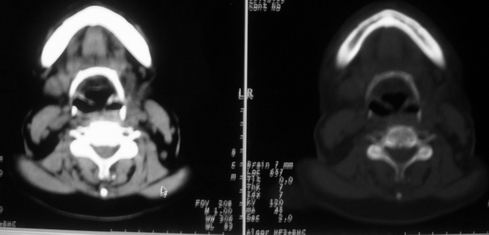

女,55岁,右侧颌下肿物3年。

右侧胸锁乳突肌后方软组织密度肿块,界限清楚。多考虑:血管源性肿瘤!

鼻咽左侧壁增厚,呈结节样突入鼻咽腔内,左侧咽隐窝消失,须考虑鼻咽癌可能,建议鼻咽纤维镜检查以明确诊断。

至于右侧颌下间隙的结节影,如果不考虑病史的话,可以诊断为淋巴结转移。但是结合病史“右侧颌下肿物3年”,又不象淋巴结转移了。建议ct增强扫描明确结节与右侧颌下腺的关系,或者穿刺活检定性。

右侧胸锁乳突肌内侧略低密度结节,应该是静内静脉而不是淋巴结。